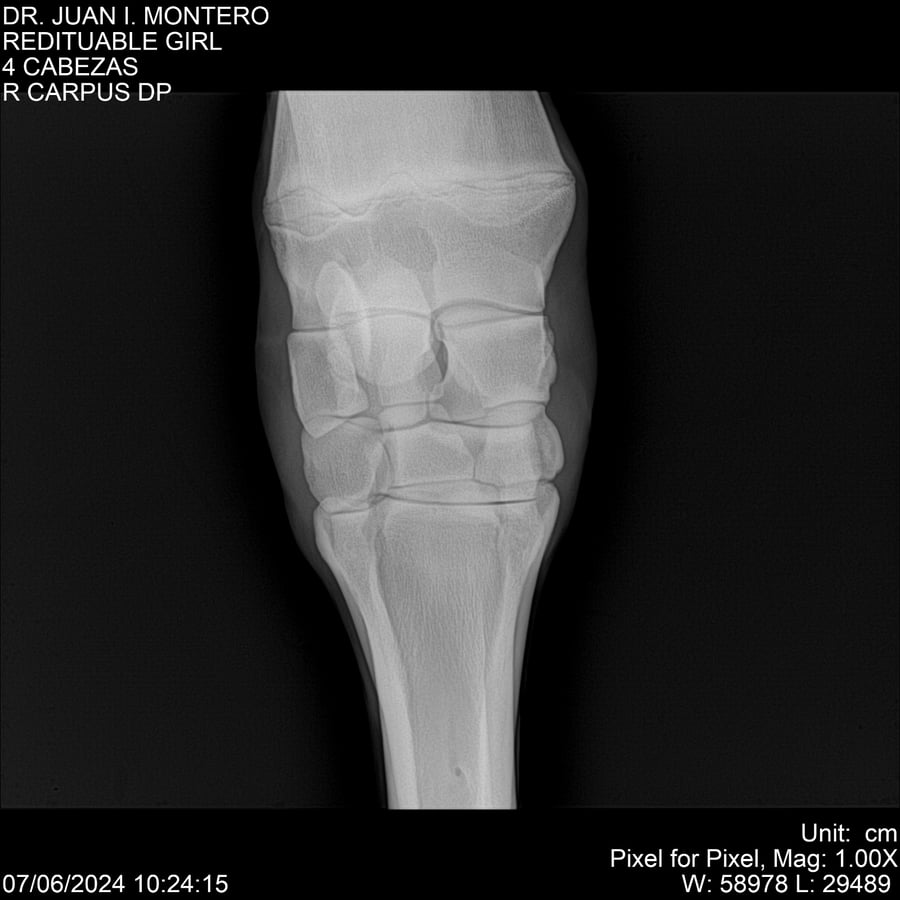

LOTE 19, REDITUABLE GIRL Lote Anterior Volver al remate Lote Siguiente Ficha Contacto Montevideo - Ficha del Lote Identificador: #281096 Categoría: Yeguarizos Montevideo - 79 Visualizaciones ClicData Contacto Empresa: Abelenda N. R., Walter Hugo Nombre*: Teléfono* : E-mail* : Mensaje Enviar Registrese gratis Este contenido Exclusivo está disponible sólo para usuarios registrados Ingresar